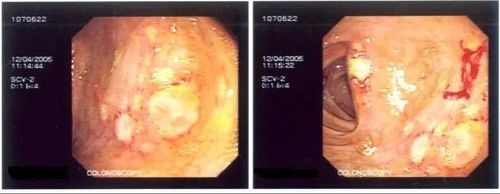

Gastrointestinal involvement develops in approximately 25% of Behcet's patients. The signs tend to appear years after the onset of oral ulcers, but gastrointestinal involvement may occur at any time. GI involvement may present with ulcers of the ileum and cecum, but any portion of the gastrointestinal tract, from mouth to anus, may be involved. The most frequent manifestations are anorexia (lack of appetite), pain, vomiting, diarrhea, and rectal bleeding. Esophageal ulcerations appear to be more common in American patients. The predilection for Behcet's Disease to involve veins may result in Budd-Chiari syndrome in some patients. Careful evaluation is essential to rule out other diseases which affect the gastrointestinal tract.